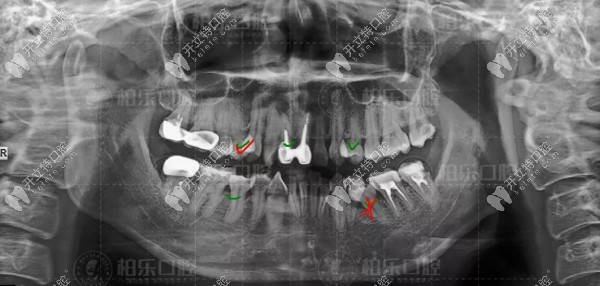

▲口腔檢查牙齒情況

去到醫(yī)院做了牙片,從牙片上很明顯可以看出,我的兩顆門牙是假牙,兩顆大牙做過(guò)根管治療,還有三顆大牙做了牙冠。

經(jīng)過(guò)一系列溝通醫(yī)生給出的方案是拔掉3顆牙,矯正時(shí)間2年多。

▲口腔檢查我的牙片